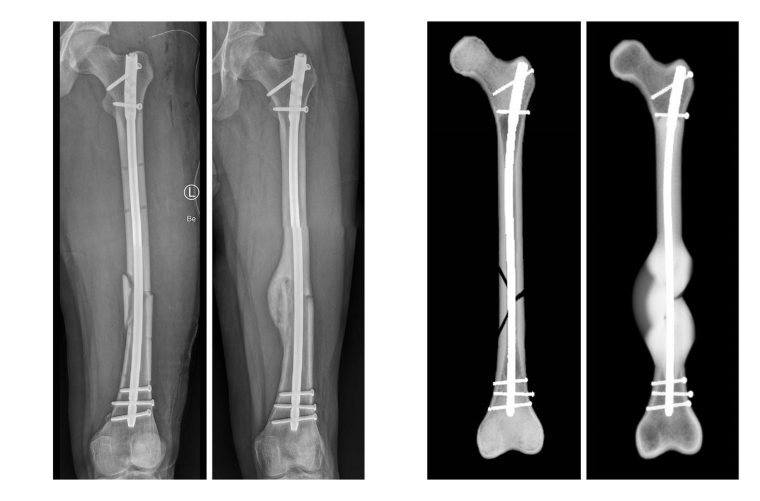

Für die Simulation wurden die klinischen Daten von 36 Patienten rückblickend analysiert. Diese hatten sich einen Schaftbruch des Oberschenkelknochens zugezogen, der durch die Implantation von Marknägeln versorgt worden war. Mithilfe von postoperativen Daten konnte die Computersimulation das Heilungsergebnis von 30 Fällen korrekt vorhersagen. „Bisherige Studien zum Ulmer Frakturheilungsmodell basierten auf Daten aus Tierversuchen oder aus Versuchen unter Laborbedingungen. Die Kooperation mit dem UKU hat es uns nun ermöglicht, das Heilungsmodell erstmalig mit klinischen Daten zu testen. So konnten wir den Prototypen des Softwaretools weiterentwickeln“, sagt Dr. Lucas Engelhardt von OSORA. „Das Heilungsmodell ist nicht nur in der Lage, Informationen zu erfolgreichen Heilungsverläufen zu generieren. Es wird ebenso zukünftig möglich sein, das Risiko für Komplikationen bis hin zu Pseudoarthrosen – also knöchernen Fehlheilungen – zu kalkulieren“, ergänzt Dr. Frank Niemeyer, ebenfalls von OSORA. Unter Berücksichtigung von patientenindividuellen Parametern, wie Größe und Gewicht, und Begleiterkrankungen, wie Osteoporose oder Adipositas, können dann Behandlungswege für jeden Patienten individuell erstellt werden. Die Simulation unterstützt so die ärztliche Expertise durch Informationen zur Belastungsfähigkeit des Knochens während der Heilung.

Lediglich in sechs Fällen – von denen zwei Knochenbrüche geheilt und vier nicht geheilt waren – war die Prognose der Computersimulation nicht korrekt. „Jeder Patient heilt anders, jede Fraktur hat ihre Besonderheiten. Wir können aus den Daten ableiten, warum die Simulation in diesen Fällen nicht den realen Frakturheilungsverlauf abbildet, um neben der Biomechanik weitere Einflüsse auf das Knochenwachstum im Modell mit zu berücksichtigen. Diese Informationen sind für die weitere Entwicklung unserer Softwareplattform von größter Bedeutung, um die Präzision der Vorhersage kontinuierlich zu erhöhen“, erklärt Dr. Lucas Engelhardt.